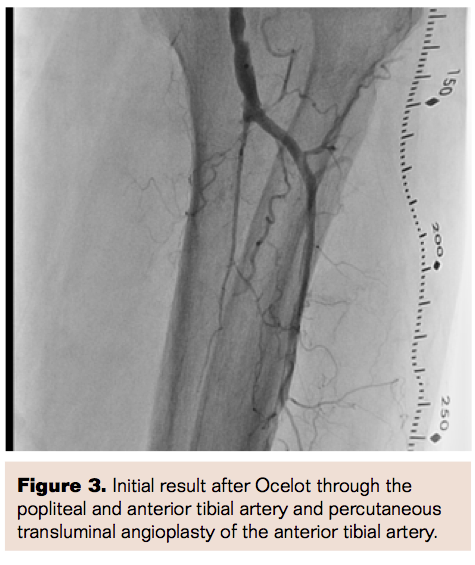

A 71-year-old male presented with multiple risk factors for cardiovascular disease and PVD, including a 60-pack-year history of smoking, hypertension, hyperlipidemia, diabetes mellitus, history of myocardial infarction, and ischemic cardiomyopathy (EF 35%). The patient presented with intermittent claudication for several years and rest pain over the last 6 months, Rutherford Class IV, with no critical limb ischemia and with ABI of 0.5 on the left leg. Angiogram of the lower extremity showed complete occlusion of the left superficial femoral artery (SFA) (Figure 1), with complete occlusion of the infrapopliteal vessels.